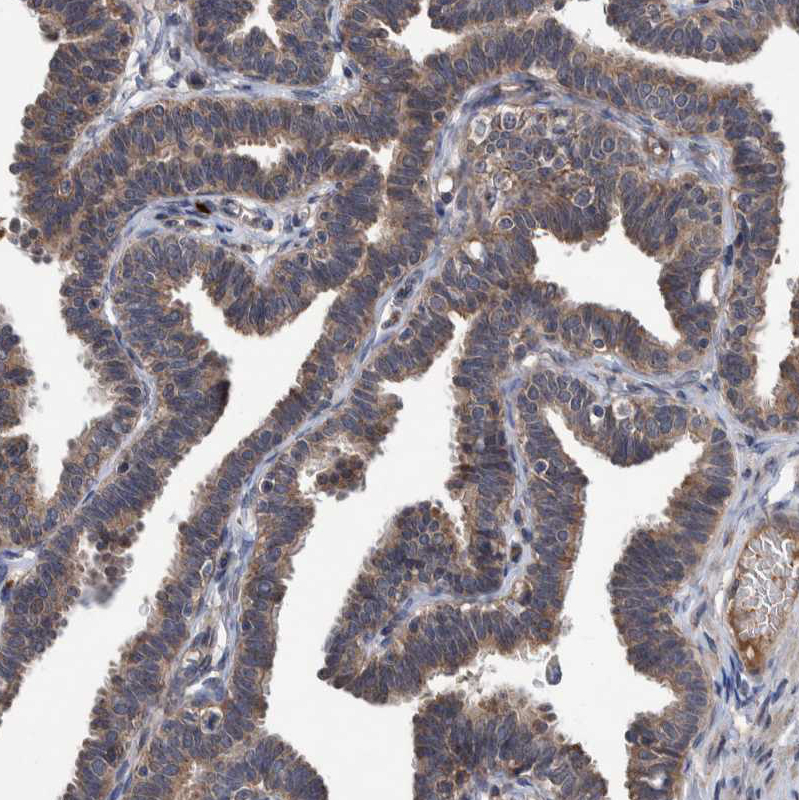

Immunohistochemical staining of human Liver shows strong cytoplasmic positivity in hepatocytes.